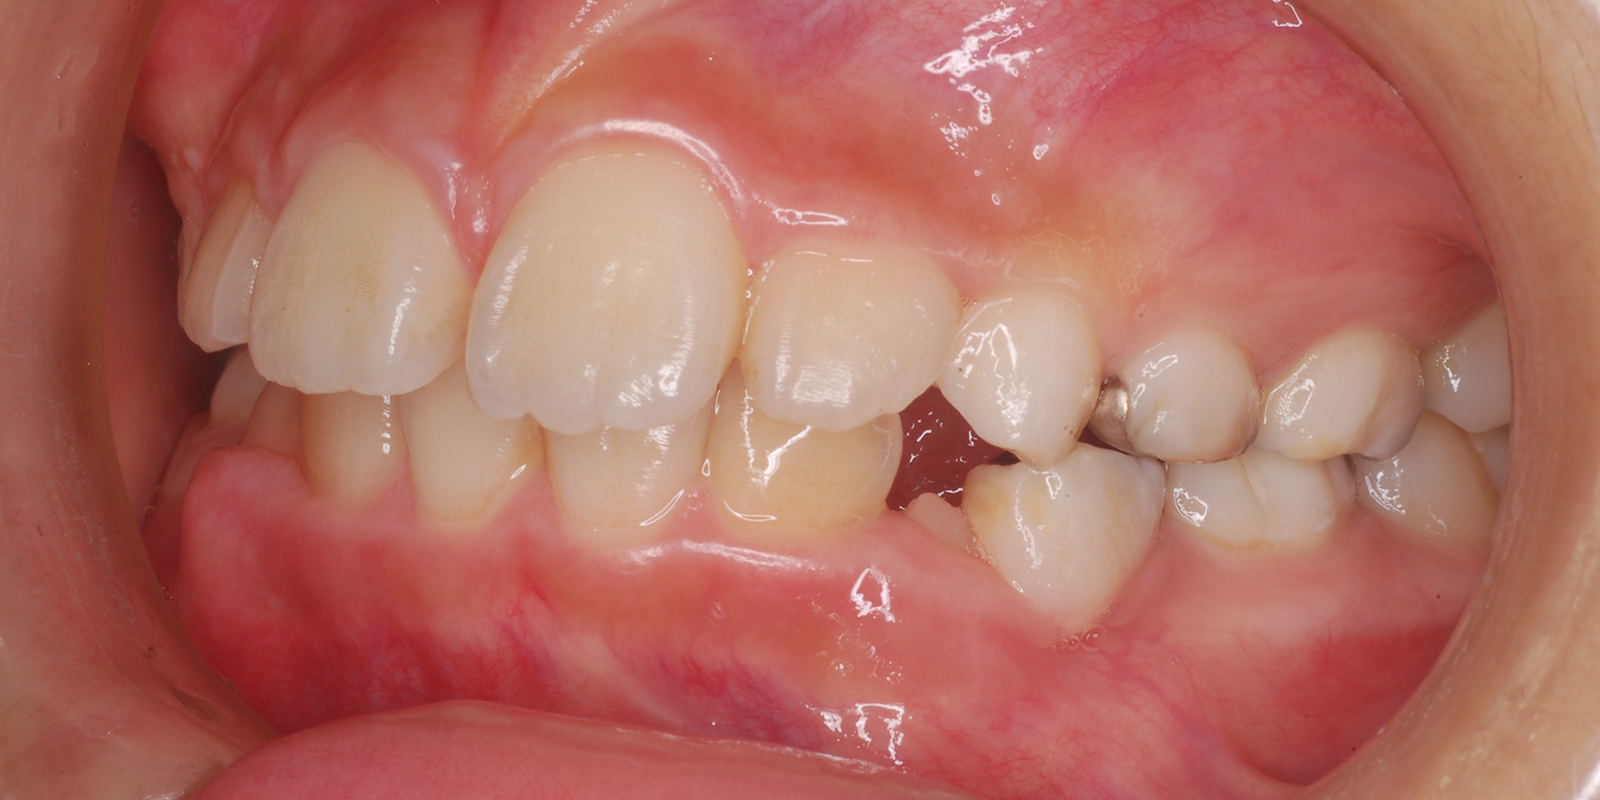

術前

| 主訴 | 叢生 |

| 診断 | アングルⅡ級1類 |

| 初診時年齢 | 9歳10か月 |

| 装置 | ヘッドギアー(1期治療) 若干上顎が大きく、大臼歯関係が上顎大臼歯が前に出て上顎前突のため、上顎大臼歯を遠心に送るためヘッドギアーを使用しました。 |

| 抜歯・非抜歯 | 上下左右第1小臼歯を抜歯、マルチブラケット(2期治療) 大臼歯関係が正しい関係になりましたが、叢生、歯軸の関係が悪いので、永久歯の抜歯を行いました。 |

| 治療期間 | 1期治療:1年10ヶ月 2期治療:3年 |

| 通院回数 | 1期治療:13回 2期治療:約36回 |

| 治療費 | 約100万円 矯正歯科治療は公的医療保険の適用外の自費(自由)診療となります |

| 治療のリスク | ・装置を使用しなければ効果が出ない ・歯に痛みが出ることがある ・取り外しのため、なくすことがある ・ブラッシングが悪い場合虫歯や歯肉炎になります |